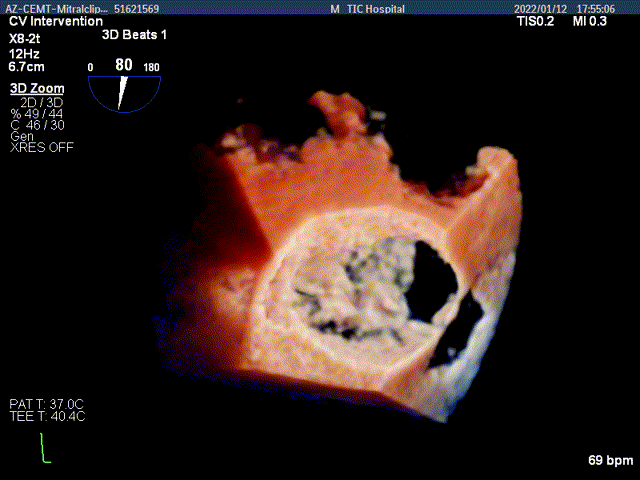

3D MV View:二尖瓣AC区为主(累及部分1区)脱垂并腱索断裂

3D-color MV view:大量返流,主要来源于AC区

Qlab软件勾画估测瓣口面积约:6.89cm2

TEE Bicom view:二尖瓣AC区为主(累及部分1区)脱垂并腱索断裂。

Color-view:大量返流,主要来源于AC区